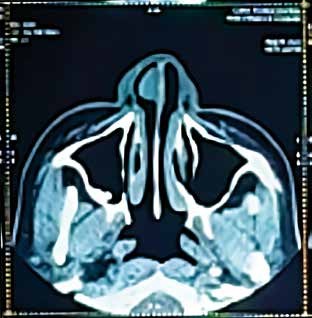

Se cuenta con tomografía computarizada sin contraste de nariz y senos paranasales que muestra en fosa nasal derecha masa ocupante, redondeada, de 1.5 mm de diámetro, isodensa con base sésil en tabique nasal (área I y II de Cottle) sin erosión ósea, además desvío septal hacia fosa nasal izquierda. (Figura Nº 2).

Figura Nº2 . Fosa nasal derecha con masa ocupante, redondeada, de 1.5 mm de diámetro, isodensa con base sésil en tabique nasal (área I y II de Cottle) sin erosión ósea